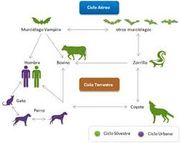

| 15:35 13 dic 2018 | Rabia Images.jpg (archivo) |  |

6 KB | 1 | |